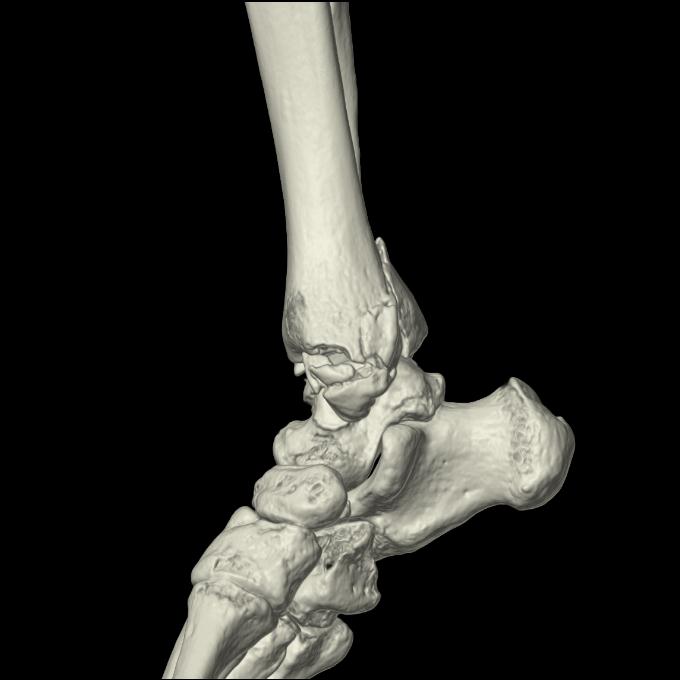

102755 1/4 2R 1/15 2R 右足関節 68歳女性 右三果脱臼骨折